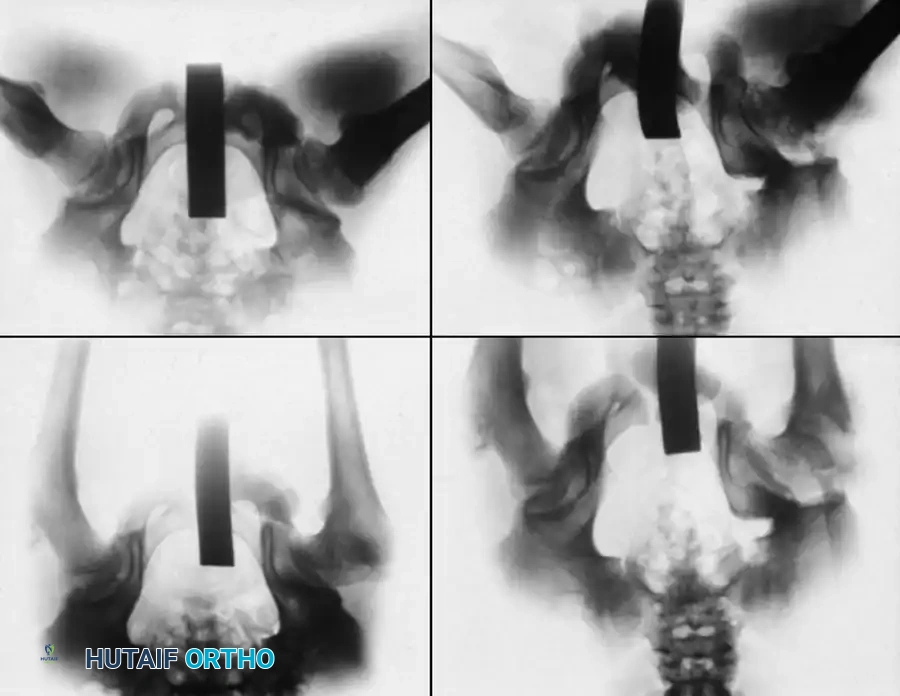

Bilateral Involvement

Bilateral LCPD occurs in 10-15% of cases and must be carefully distinguished from Multiple Epiphyseal Dysplasia (MED). Skeletal surveys and bone age assessments are critical here.

While early literature suggested bilateral cases were inherently more severe, Guille et al. evaluated 83 patients and found that the development of bilateral LCPD represents two independent ischemic events. The second hip affected is generally less severe (78% of cases), and the Stulberg outcome is independent of bilaterality. Unilateral disease does not predispose the contralateral hip to a more severe disease course.

Innominate osteotomies, such as the Salter osteotomy, provide containment by redirecting the acetabulum to cover the anterolateral aspect of the femoral head without altering the proximal femoral anatomy. This is particularly advantageous in older children where remodeling of a varus femur is less predictable, or in cases where limb shortening is undesirable.

Salter Innominate Osteotomy Technique:

1. Approach: A Smith-Petersen (anterior) approach is utilized. The interval between the tensor fasciae latae and the sartorius is developed.

2. Exposure: The iliac apophysis is split, and the inner and outer tables of the ilium are stripped subperiosteally down to the greater sciatic notch.

3. Osteotomy: A Gigli saw is passed through the sciatic notch and directed anteriorly to exit at the anterior inferior iliac spine (AIIS).

4. Redirection: The distal acetabular fragment is hinged on the pubic symphysis and rotated anterolaterally, pivoting on the triradiate cartilage.

5. Grafting and Fixation: A triangular wedge of bone (harvested from the anterior iliac crest) is impacted into the osteotomy gap. The construct is stabilized with two or three threaded Kirschner wires driven from the proximal ilium, through the graft, and into the distal fragment.